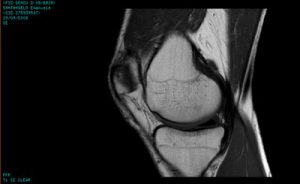

La risonanza magnetica (RM) è una tecnica diagnostica multiparametrica che fornisce immagini dettagliate del corpo umano utilizzando campi magnetici e onde radio, senza esporre il paziente a nessun tipo di radiazioni. Le informazioni fornite dalle immagini di risonanza magnetica sono essenzialmente di natura diversa rispetto a quelle degli altri metodi di imaging. Infatti sono normalmente meglio esaminabili i tessuti molli ed è inoltre possibile la discriminazione tra tipi di tessuti non apprezzabile con altre tecniche radiologiche.

Viene utilizzata per la diagnosi di una grande varietà di condizioni patologiche perché permette di visualizzare sia lo scheletro/articolazioni e muscoli, sia gli organi interni, attraverso l’acquisizione di sequenze di immagini che consentono di distinguere un tipo di tessuto da un altro ed ancora una componente tissutale patologica da una sana.

Questo esame diagnostico ricostruisce una rappresentazione delle strutture interne del corpo ad alta risoluzione ed assolutamente affidabile,  che corrisponde alla reale anatomia, con una eccellente risoluzione spaziale e conseguente possibilità di eseguire accurate misurazioni.

Queste caratteristiche intrinseche alla metodica permettono di distinguere tra loro i tessuti e riconoscere quelli danneggiati.

Nello studio della patologia muscolo-scheletrica e quindi delle strutture articolari/capsulo/meniscali e dei legamenti così come per valutare l’edema osseo la metodica più indicata è quella della RMN, anche rispetto all’ecografia ed ovviamente alla Radiologia Tradizionale proprio in virtù delle caratteristiche intrinseche sopra descritte.